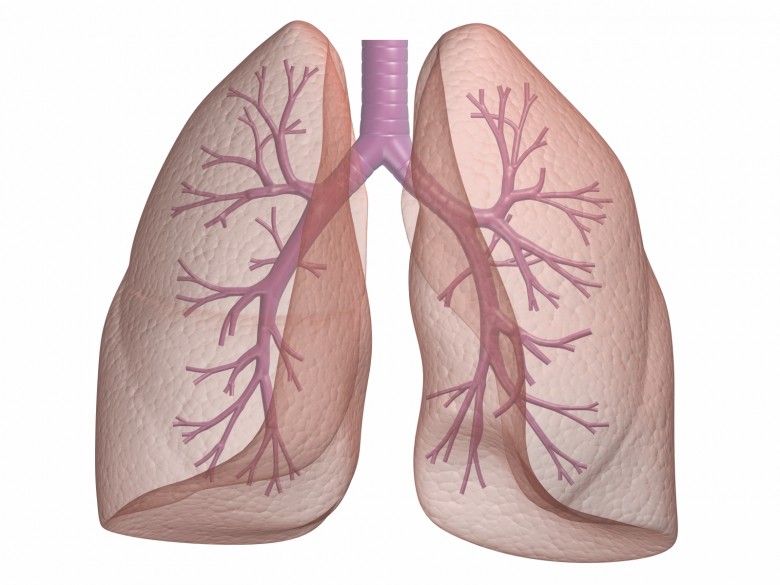

Καρκίνος του πνεύμονα: Θεραπεία για τα μη χειρουργήσιμα στάδια

Ο καρκίνος του πνεύμονα είναι μια συχνή αιτία θανάτου, ενώ η χειρουργική αντιμετώπιση αποτελεί θεραπεία εκλογής στα αρχικά στάδια της νόσου. Τα τελευταία χρόνια και με την αλματώδη ανάπτυξη της τεχνολογίας τόσο των ακτινοθεραπευτικών όσο και των ακτινοδιαγνωστικών μηχανημάτων, είναι εφικτή η αντιμετώπιση των πρώιμων σταδίων και με μη επεμβατικές μεθόδους όπως η στερεοτακτική ακτινοθεραπεία.